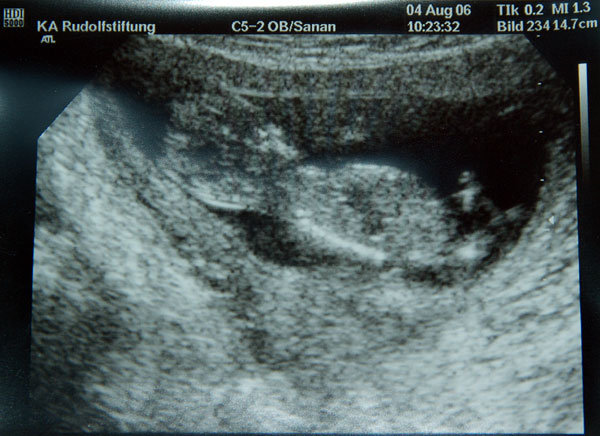

Andusz, cuki a kep!!!!!

Meretek:

Tarkoredo: 1,2 mm

Korom 29 ev ugyibar, korbol szamitott esely 21-es trisomiara 1:704, esely 13/18-as triszomiara 1:1295

A meresbol szamitott esely: 1: 3794, es 1:12210

Korunk: 12+5

Babszem 12+5

Magzat: 64 mm

Minden a helyen.

Tiszta anyja a pici, nem akart befordulni, mar utogette az UH- keszulekkel jo durvan a pocimat a csaj, mert mindenfele mozgott Babszem, csak arra nem, amerre kellett volna. Na, erre mar csak azert sem mutatta a nyakat...

Meretek, szervek, sziv, koponya, vegtagok rendben.